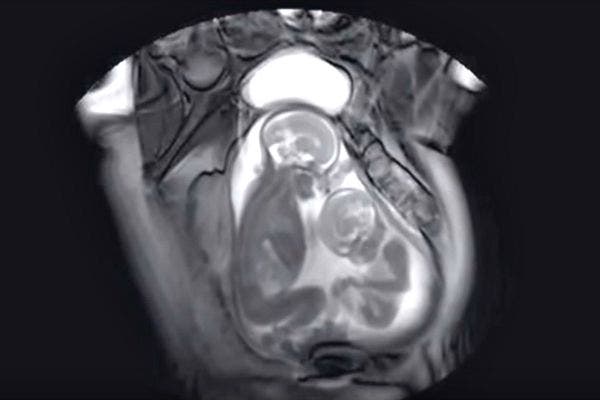

The MRI machine also captured a baby in utero. It's pretty amazing how much detail you can see on the baby — fingers, toes, eyes, and brain.

5. And sometimes, they're extra lucky and make two babies at once.

What's better than one baby? Two, of course! And you can already see who the bossy twin will be.